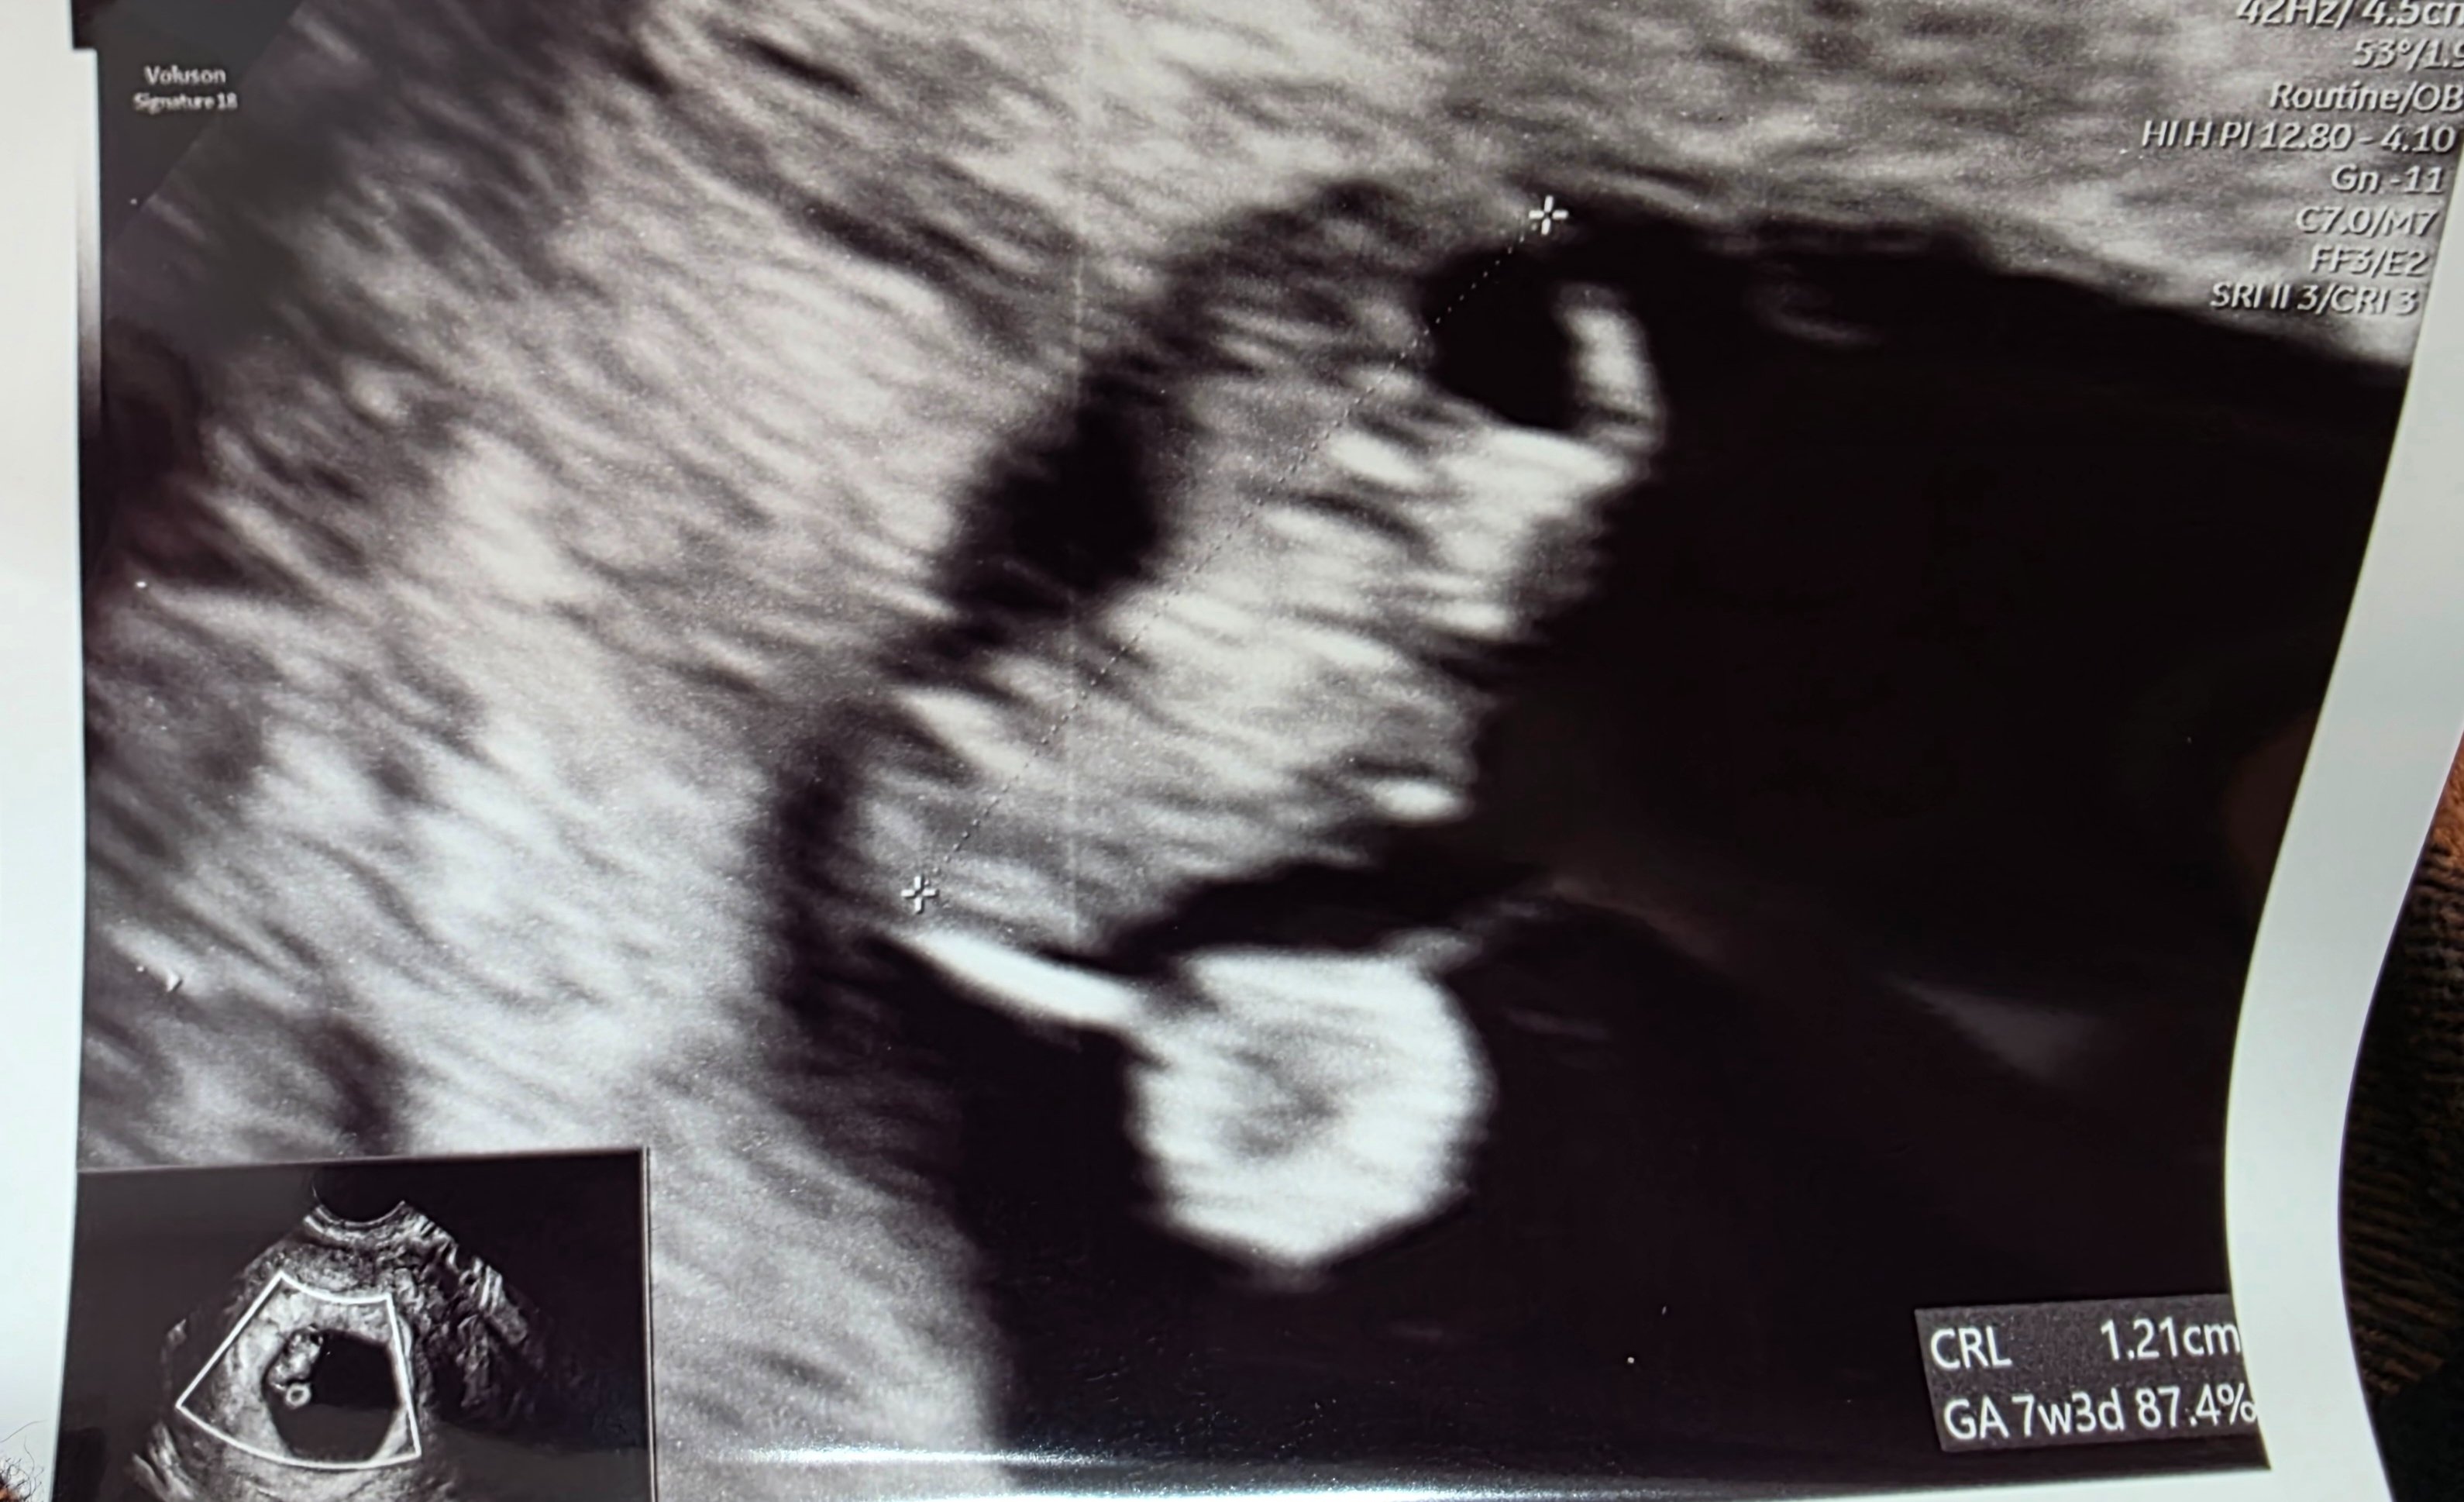

Jestem po USG.

Maluszek ma 12mm co odpowiada dokładnemu wiekowi wg daty porodu. 7tyg+3dni❤️❤️

Serduszko bije 151ud/min

Lekarz powiedział, że na tym etapie jest wszystko super. Ze względu na poprzednia stratę dla mojego spokoju zalecił powtórne USG za 2 tyg. wizyta 09.04.